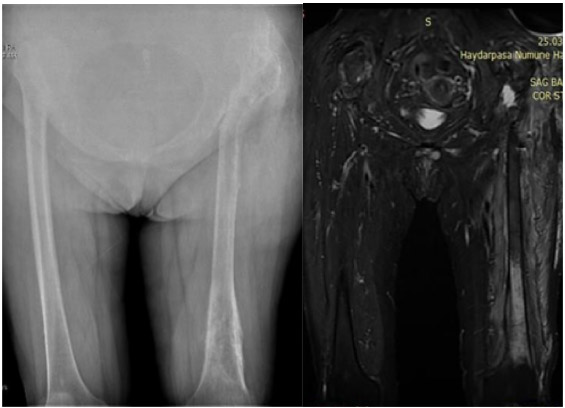

Before the surgery: X-rays show osteoarthritis on a base of high dislocation in both hips and failure of the distal end of the left femur; MRI shows edema surrounding a metastatic focus in the same location.